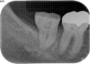

当時の歯の移植は、移植歯を抜歯したら、歯の根の表面の徹底的な清掃(掻爬)と、根管治療を口腔外で行いその歯を移植していました。しかし、それでは移植歯は移植された所の歯槽骨(もともとの歯を支える骨)とどんなに上手くいっても骨性癒着を起こします。この癒着した歯の根は時間と共に周囲の骨組織に吸収され、やがて歯の根はあとかたも無くレントゲンから消え去り、まるで乳歯が抜けるように根の無くなった歯が抜けていきます。これが5年もてば成功といわれた所以です。

現在は、ドナーとなる歯の抜歯前に移植される側の処置を終了し、ドナーの歯を抜歯するとほぼ同時に、当院では3秒以内に受容側の中にドナーの歯を入れます。これはとても速いスピードであるといえ、このスピードで確実に行う為に、いろいろな研究を行い、CTスキャンのデータを応用した現在の移植のシステムを構築致しました。

このようにして移植された歯は、歯の根の表面にある歯根膜と言う組織がほぼ完全に保存され、生着(生きた状態で移植されて機能する事)する事によって、将来矯正治療で歯を移動する事もできますし、被せもの等を行えば全く移植歯である事は気が付かれないレベルで仕上がります。